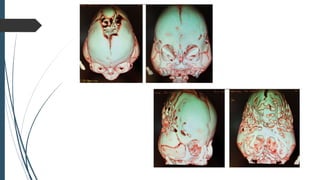

• #57 Tomografía craneal con reconstrucción 3D: severa sinostosis con compromiso de sutura metópica, coronal y lambdoidea, áreas de craneola- cunias e hipertensión endocraneal.

VARÓN DE 6MESES: ALTERACIÓN EN MORFOLOGÍA CRANEAL CON ASPECTO TRILOBULAR, ABULTAMIENTO TEMPORAL Y CRÁNEO POSTERIOR PLANO, OREJAS DE IMPLANTACIÓN BAJA, HIPERTELORISMO, HIPOPLASIA EN TERCIO MEDIO FACIAL Y RETROGNATIA MANDIBULAR.

• 58.